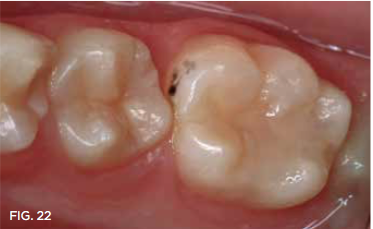

Case 5. A bite wing radiograph (not shown) revealed a distal caries lesion on a mandibular molar in a 10-year-old girl. The girl's father was informed of the need for treatment to avoid caries spread to the mesial surface of the permanent first molar. He readily agreed to SDF application rather than Class II restoration, so that his daughter could avoid a local anesthetic injection and he could save the expense. With cotton roll isolation and no local anesthetic injection, the distal caries lesion was exposed using a high-speed diamond bur (Figure 18 and Figure 19). Only one application of SDF was used in this case, followed by application of fluoride varnish (Figure 20 and Figure 21). In 7 months, the primary second molar had exfoliated, and only a trace of SDF stain remained on the permanent molar (Figure 22).

Fig 22.  7 months after SDF treatment, second molar had exfoliated.

Fig 22